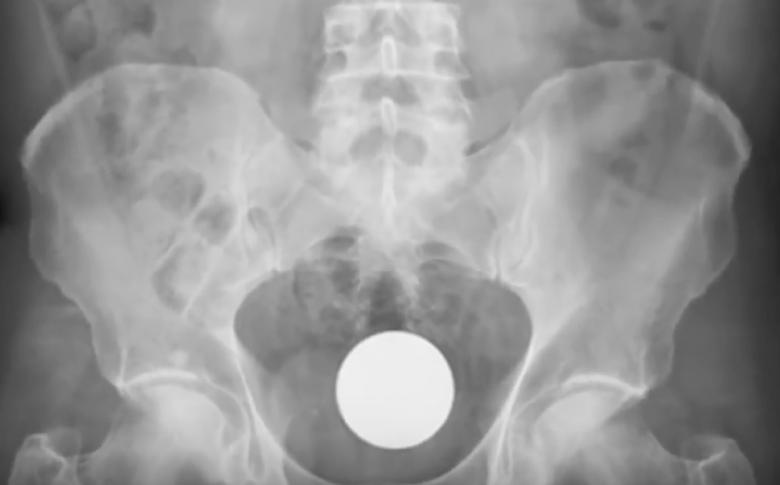

골프공은 또 뭡니까...